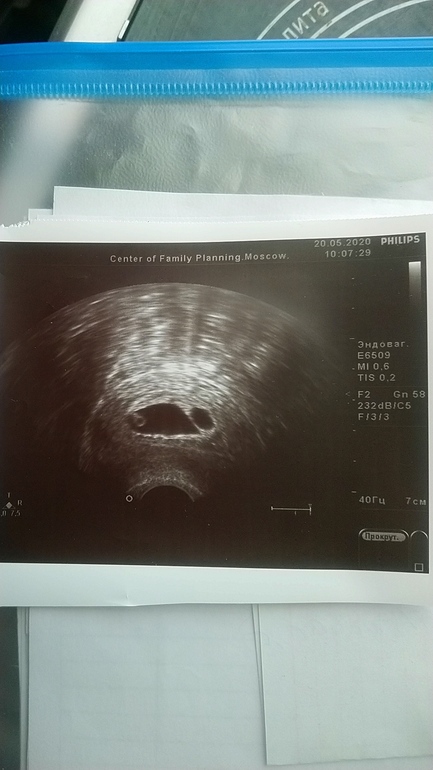

Замершая и внематочная беременностьПривет, девочки. На понедельник назначена чистка. Анэмбриония. В понед. будет срок 7н5д. В 6 недель ПЯ было пустое, в 7н по описанию узи размер ПЯ 19мм и желт. мешочек 4мм, ждать уже нечего, да и к тому же ПЯ с перегородкой(это тоже не норма, как сказал врач). Записали на чистку в самом ЦПСиР(Москва). Смущает, что по умолчанию делали бы простую чистку, когда я спросила про вакуум, то начали узнавать и сказали, что делают, но нужно предупредить обязательно. Перед самой чисткой узи там не делают, поэтому Ре сказала заскочить к ней на узи, для успокоения совести(но надежды, как она сказала нет "совсем" ) Теперь у меня сомнения: точно ли там хорошо делают? Очень боюсь последствий, вдруг в итоге сделают простую чистку или вакуум плохо 🙈Отзывов что-то не нашла. Страхов куча. У меня вопрос: кто делал вакуум(особенно по омс) ? какие последствия у Вас были? как долго восстанавливались? через сколько потом пошли снова в крио(не хочется затягивать). P.S. был крио на згт, подсаживали 1эмбр. 4АВ. Про МА Ре как-то вскользь упоминула, и то только когда я спросила. Сказала ну да, в принципе тоже можно и всё на этом. В общем любые отзывы будут полезны. Спасибочки.